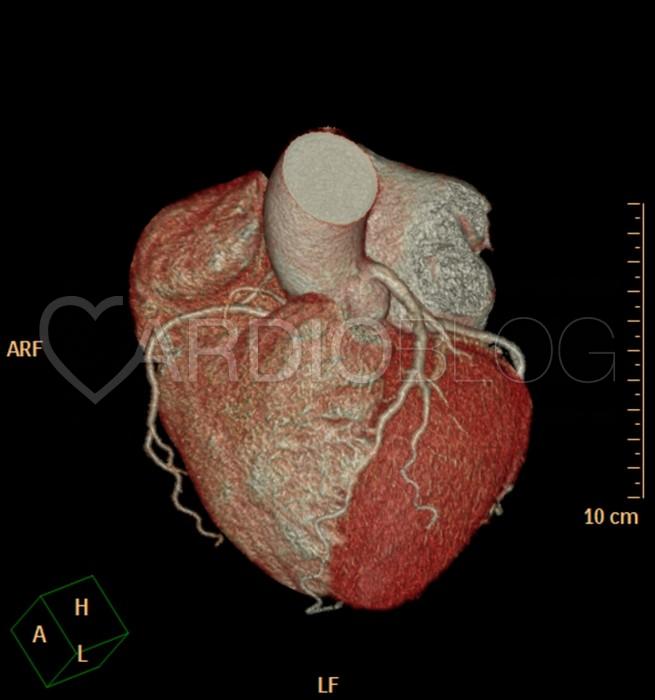

<h6>Szívtranszplantációt követő kontroll CCTA vizsgálat – LAD-ról készült kanyarodó multiplanáris rekonstrukció.</h6>

<h6>A – 1 éves után követés során a LAD proximalis szakaszán minimális fokú coronaria stenosist okozó részben calcificalt lézió igazolódott<br />

B – 2 éves után követés során a LAD proximalis és középső szegmentai érintő diffúz, koncentrikus, mérsékelt fokú szűkületet okozó coronaria betegség azonosítható.<br />

(LV – left vetricle, FUP – follow-up)</h6>